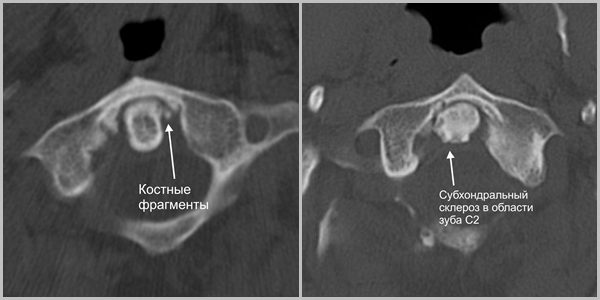

- В головах и верхнешейном отделе позвоночника выявляется картина артроза Крювелье: краевые разрастания суставных поверхностей сустава.